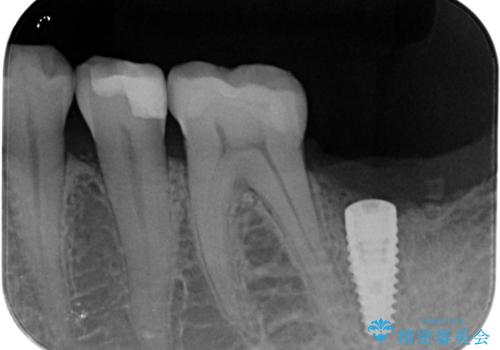

X線検査を行ったところ、セラミッククラウン下に虫歯が再発し、歯の破折も認めました。

歯の抜去を行い、骨の造成を含めたインプラントによる咬合機能の回復を図ります。

X線を撮ることで、外から見てもわからない、歯の問題点をより正確に把握することができます。